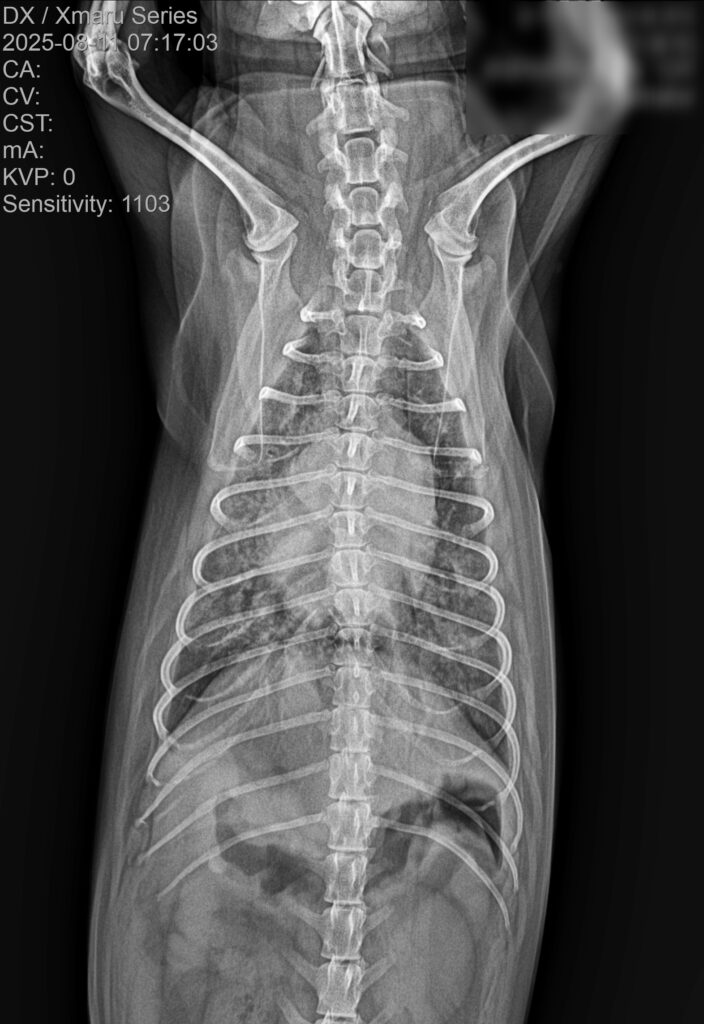

3. 흉부 방사선(X-ray) 검사

흉부 방사선 검사에서는 폐야 전반에 걸친 광범위한 침윤 소견이 관찰되었습니다.

내원 당시 흉부 방사선 사진/ 출처: 강서YD동물의료센터